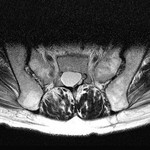

仙骨嚢腫のMRI 2010-04-23

2010-04-23

[画像診断]仙骨嚢腫のMRI

(詳細は「タカ派の画像診断医」へ)